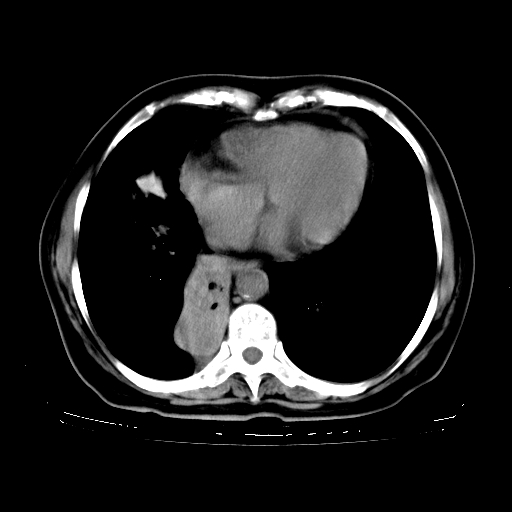

标题: CT23067:女,70岁,咳嗽、咳痰一个月,低热一周。 [打印本页]

女,70岁,咳嗽、咳痰一个月,低热一周。

1.左上肺结核,部分纤维化。右肺中下叶部分肺不张,内见液化、坏死及点状钙化,右中下叶支气管壁增厚、管腔狭窄,见多个点状钙化,结合临床考虑支气管内膜结核,建议痰检查抗酸杆菌并参考血沉。两肺多个小圆点状高密度灶,境界模糊,多考虑结核肺内播散。但本人年龄较大首先应支气管镜检以除外右肺癌。

2.胸主动脉夹层。

支持,首先一元论解释。胸主动脉部分层面环形低密度,中心强化。环形影不强化。不象真假腔的改变。我考虑动脉炎,不太支持夹层动脉瘤-和大家的观点不一致,希望楼主让患者再做个心血管的彩超吧。